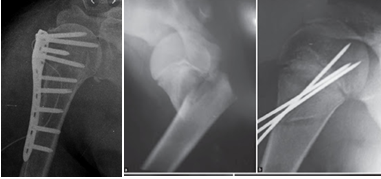

* Phương pháp

- Kết xương nẹp vít:

- Xuyên đinh Kirschner